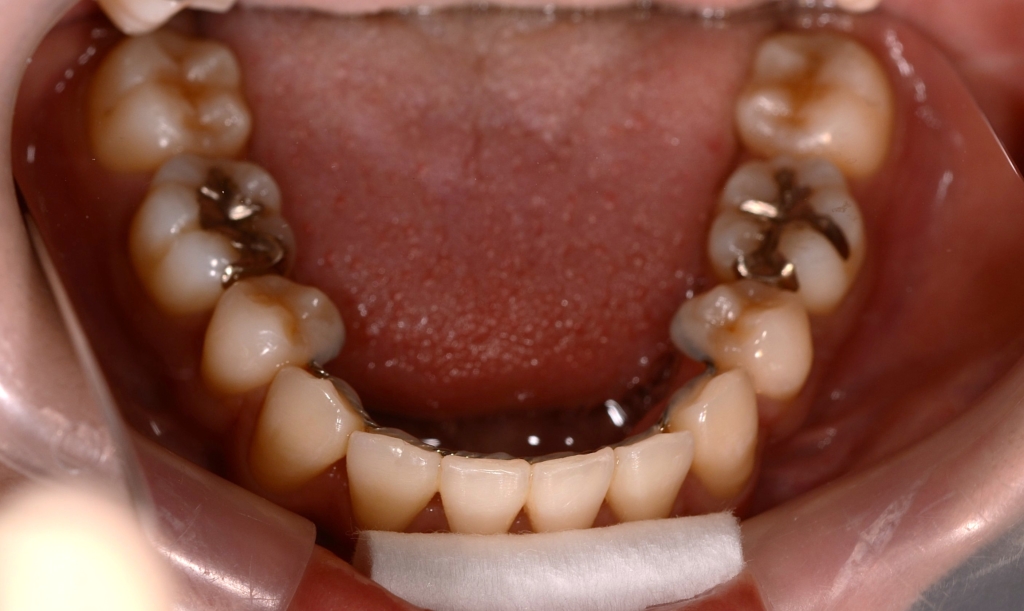

ついでに、歯並びの比較です

上段が矯正治療前、下段が矯正治療後